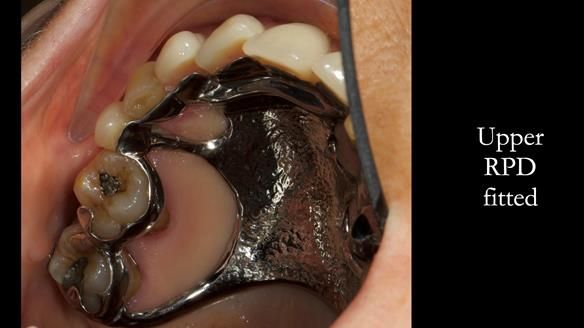

Jean’s Class I Mod III RPD: Learning from My Mistakes – From a Fractured Mk1 to a Stronger Mk2 (4 Years On)

In this edition, I present the removable partial denture treatment for Jean, an 80-year-old woman with a sore mouth caused by a soft tissue-supported 'gum stripper' acrylic denture and a clenching habit. Below, I outline the step-by-step process of her treatment. It wasn't straightforward; I had to remake the denture after it fractured to achieve a satisfactory result. Each patient is unique, and sometimes a new RPD serves as a prototype. Occasionally, I need to make adjustments, learn from any mistakes, and refine the design to get it right.

The treatment has been a success over the past 4 years.